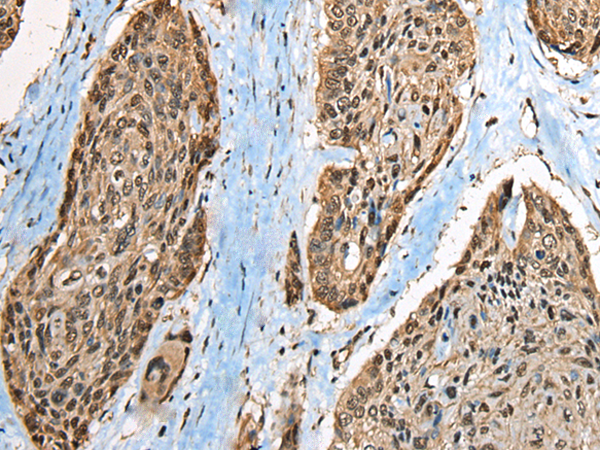

分类: 科研抗体货号: P02443别名: CT3; CT95; CTAG3; bA69L16.7应用: WB,IHC反应种属: Human